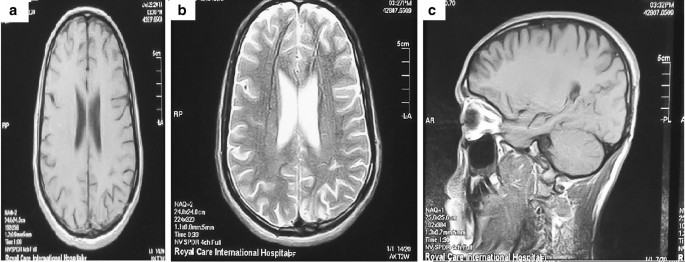

A 24-year-old, previously healthy Afro-asiatic man presented to our neurosurgical outpatient clinic complaining of headache for 3 months, which was followed by one attack of generalized tonic–clonic convulsions, which prompted him to seek medical advice. He reported no other associated signs or symptoms. Upon general examination, the patient looked unwell, but no pallor, jaundice, or cyanosis was observed. His vital signs were all within the normal range. On neurological examination, he was conscious, oriented to time, place, and person, with a Glasgow Coma Scale score of 15 out of 15 and normal papillary reaction and size bilaterally. The patient had power grade 4+ in both the upper and lower right limbs, with normal tone and reflexes in all joints. Systemic review was unremarkable. Laboratory investigations including stool and urine general test results were unremarkable, so no further cerebral spinal fluid analysis was pursued. Initial plain head computed tomography (CT) showed a focal area of high density within the left parietal region. An MRI of the brain was then performed and showed a fairly well-defined 1.8 × 1 cm lobulated, cortical-based intra-axial lesion within the left posterior parietal region. The lesion demonstrated homogeneous enhancement and had associated moderate perilesional vasogenic edema with only a mild localized mass effect. No other focal lesions were seen (Fig. 1). A list of possible differential diagnoses was made and included granulomatous lesion, lymphoma, a primary glial neoplasm, and less likely meningioma.

MRI brain showed left posterior parietal homogenous 1.8x1cm enhancing lesion in a) axial T1WI with peri-focal oedema. Lesion fairly defined, irregular, lobulated, intra-axial, cortical based rather than dural based, hyper-intense in b) axial T2WI and moderate size peri-lesional oedema in c) sagittal T1WI with contrast